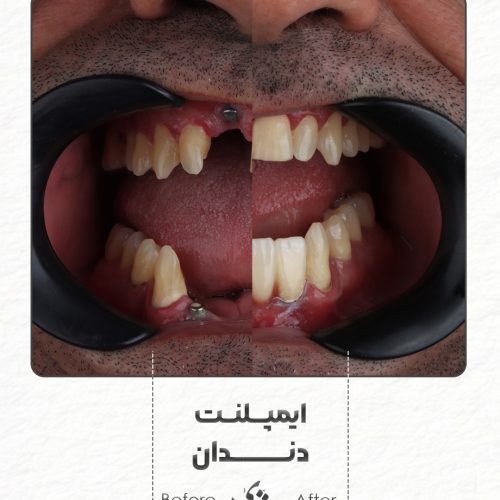

– اوردنچر

– دندان مصنوعی

– ایمپلنت